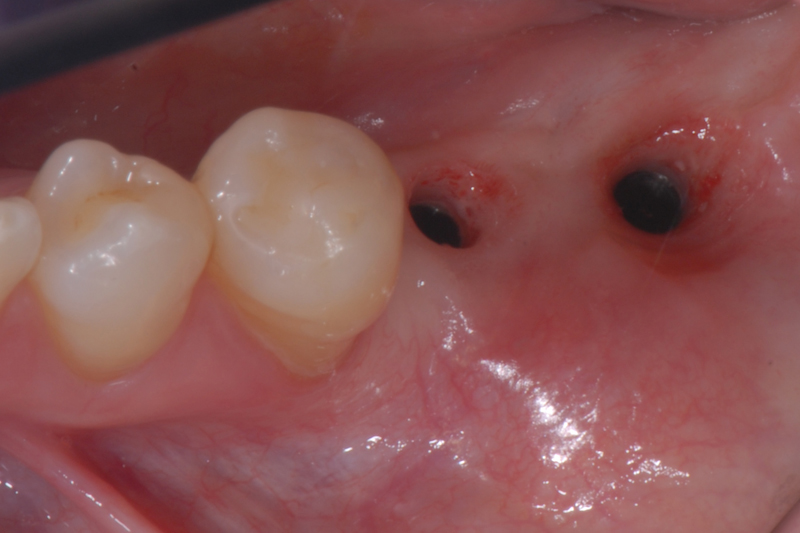

- Status kliniczny przed fazą protetyczną